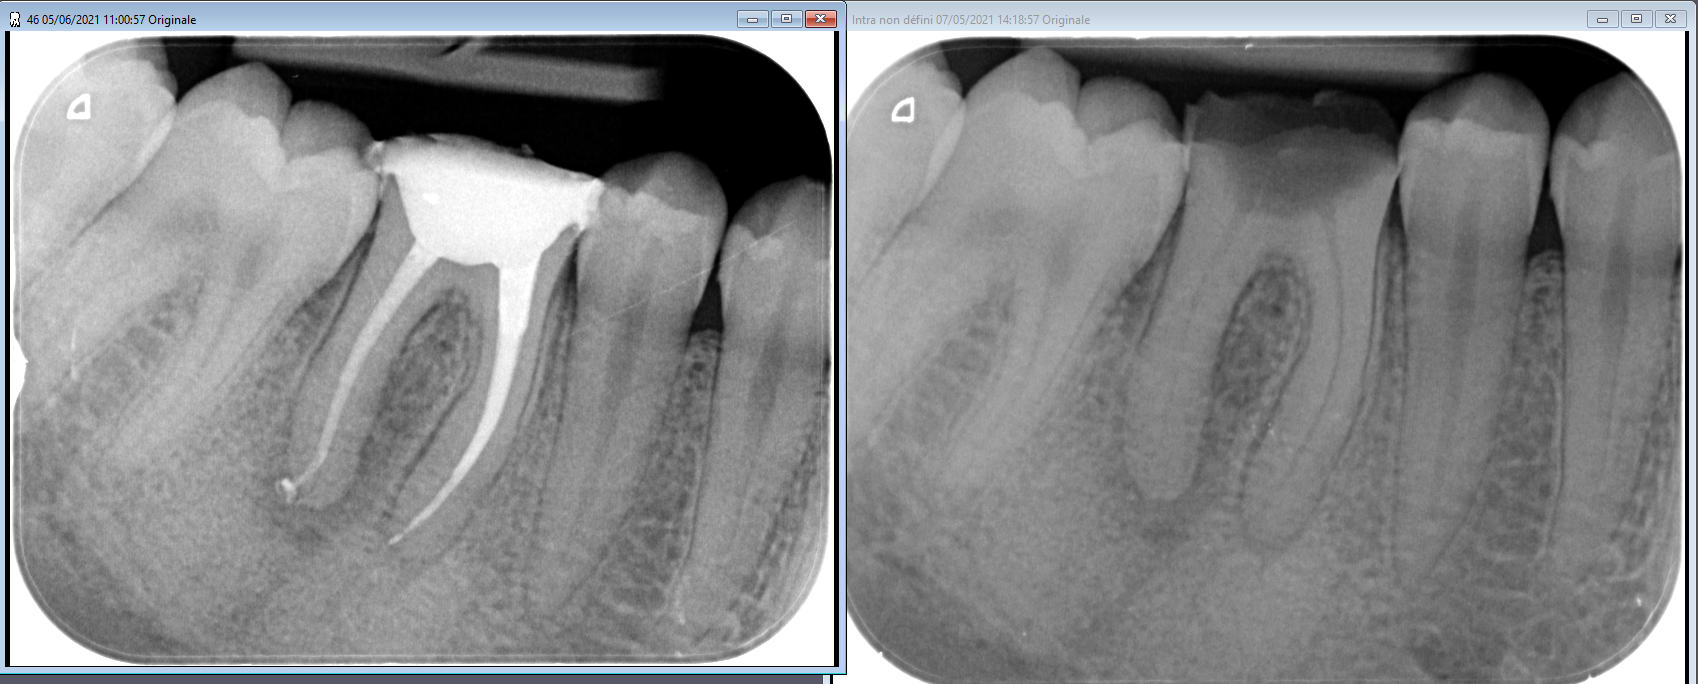

cette semaine y'a deux cas d'endo ou j'ai pas posé de digue... juste optragate+lingua fix... je vais aller en prison ;)

Sans digue butl0j - Eugenol

Sans digue 1 gntkz3 - Eugenol